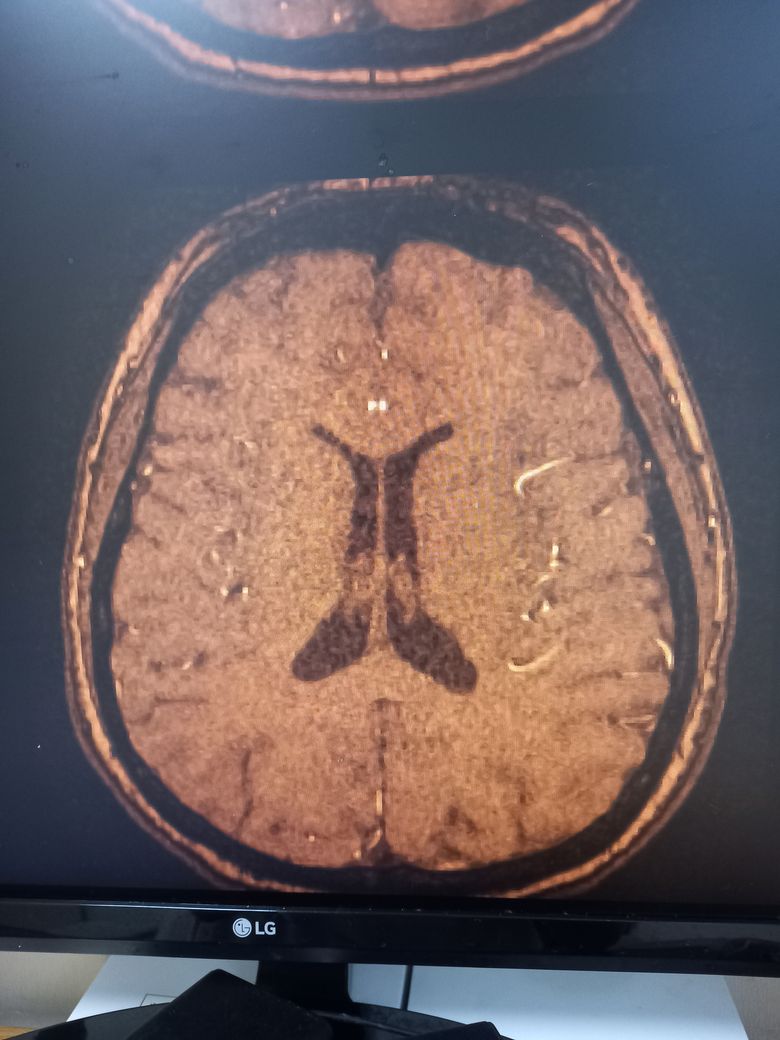

건강검진 mra 사진인데 아직 결과 안나왓고 씨디만 받아온건데 집에서 보다보니 궁금해서요 저 하얗개 지저분한거 원래도 찍으면 나오나요?? 아님 저거 뭐애요?

안녕하세요. 이욱현 의사입니다. 혈관이 찍여서 보인 것으로 보입니다.

이렇게 정상적으로 혈관들이 보입니다. 혈관이 뇌 사이사이를 지나기 때문에 혈관 일부가 보이는 소견으로 보입니다.

혈관 조영제를 사용한 결과입니다. 하얗게 보이는 것은 혈관이 보이는 거에요. 정상인 것이지요.